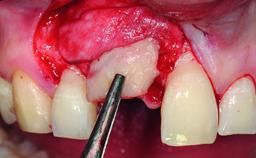

A 32-year-old female Caucasian patient with a compromised maxillary right central incisor was referred to us by a general dentist. Her chief complaints were discomfort and mobility of tooth 11 with unsatisfactory esthetics due to discoloration. The patient reported a previous trauma, some years earlier, as the origin of pathology on the afflicted tooth. Anamnesis was negative for any other dental or periodontal pathology in the remaining dentition. The patient did not take any medication and reported to be a light smoker (5–10 cigs/day). She had high esthetic expectations of her treatment. The extraoral examination revealed a high smile line with full exposure of her maxillary teeth and surrounding soft tissue in the area between the second premolars.

Bone Augmentation Horizontal|Simultaneous|Staged

Augmentation Materials Autogenous chips|Xenogenous|Membrane

Soft Tissue Grafting Staged

Bone Volume Deficient horizontally, requiring prior grafting